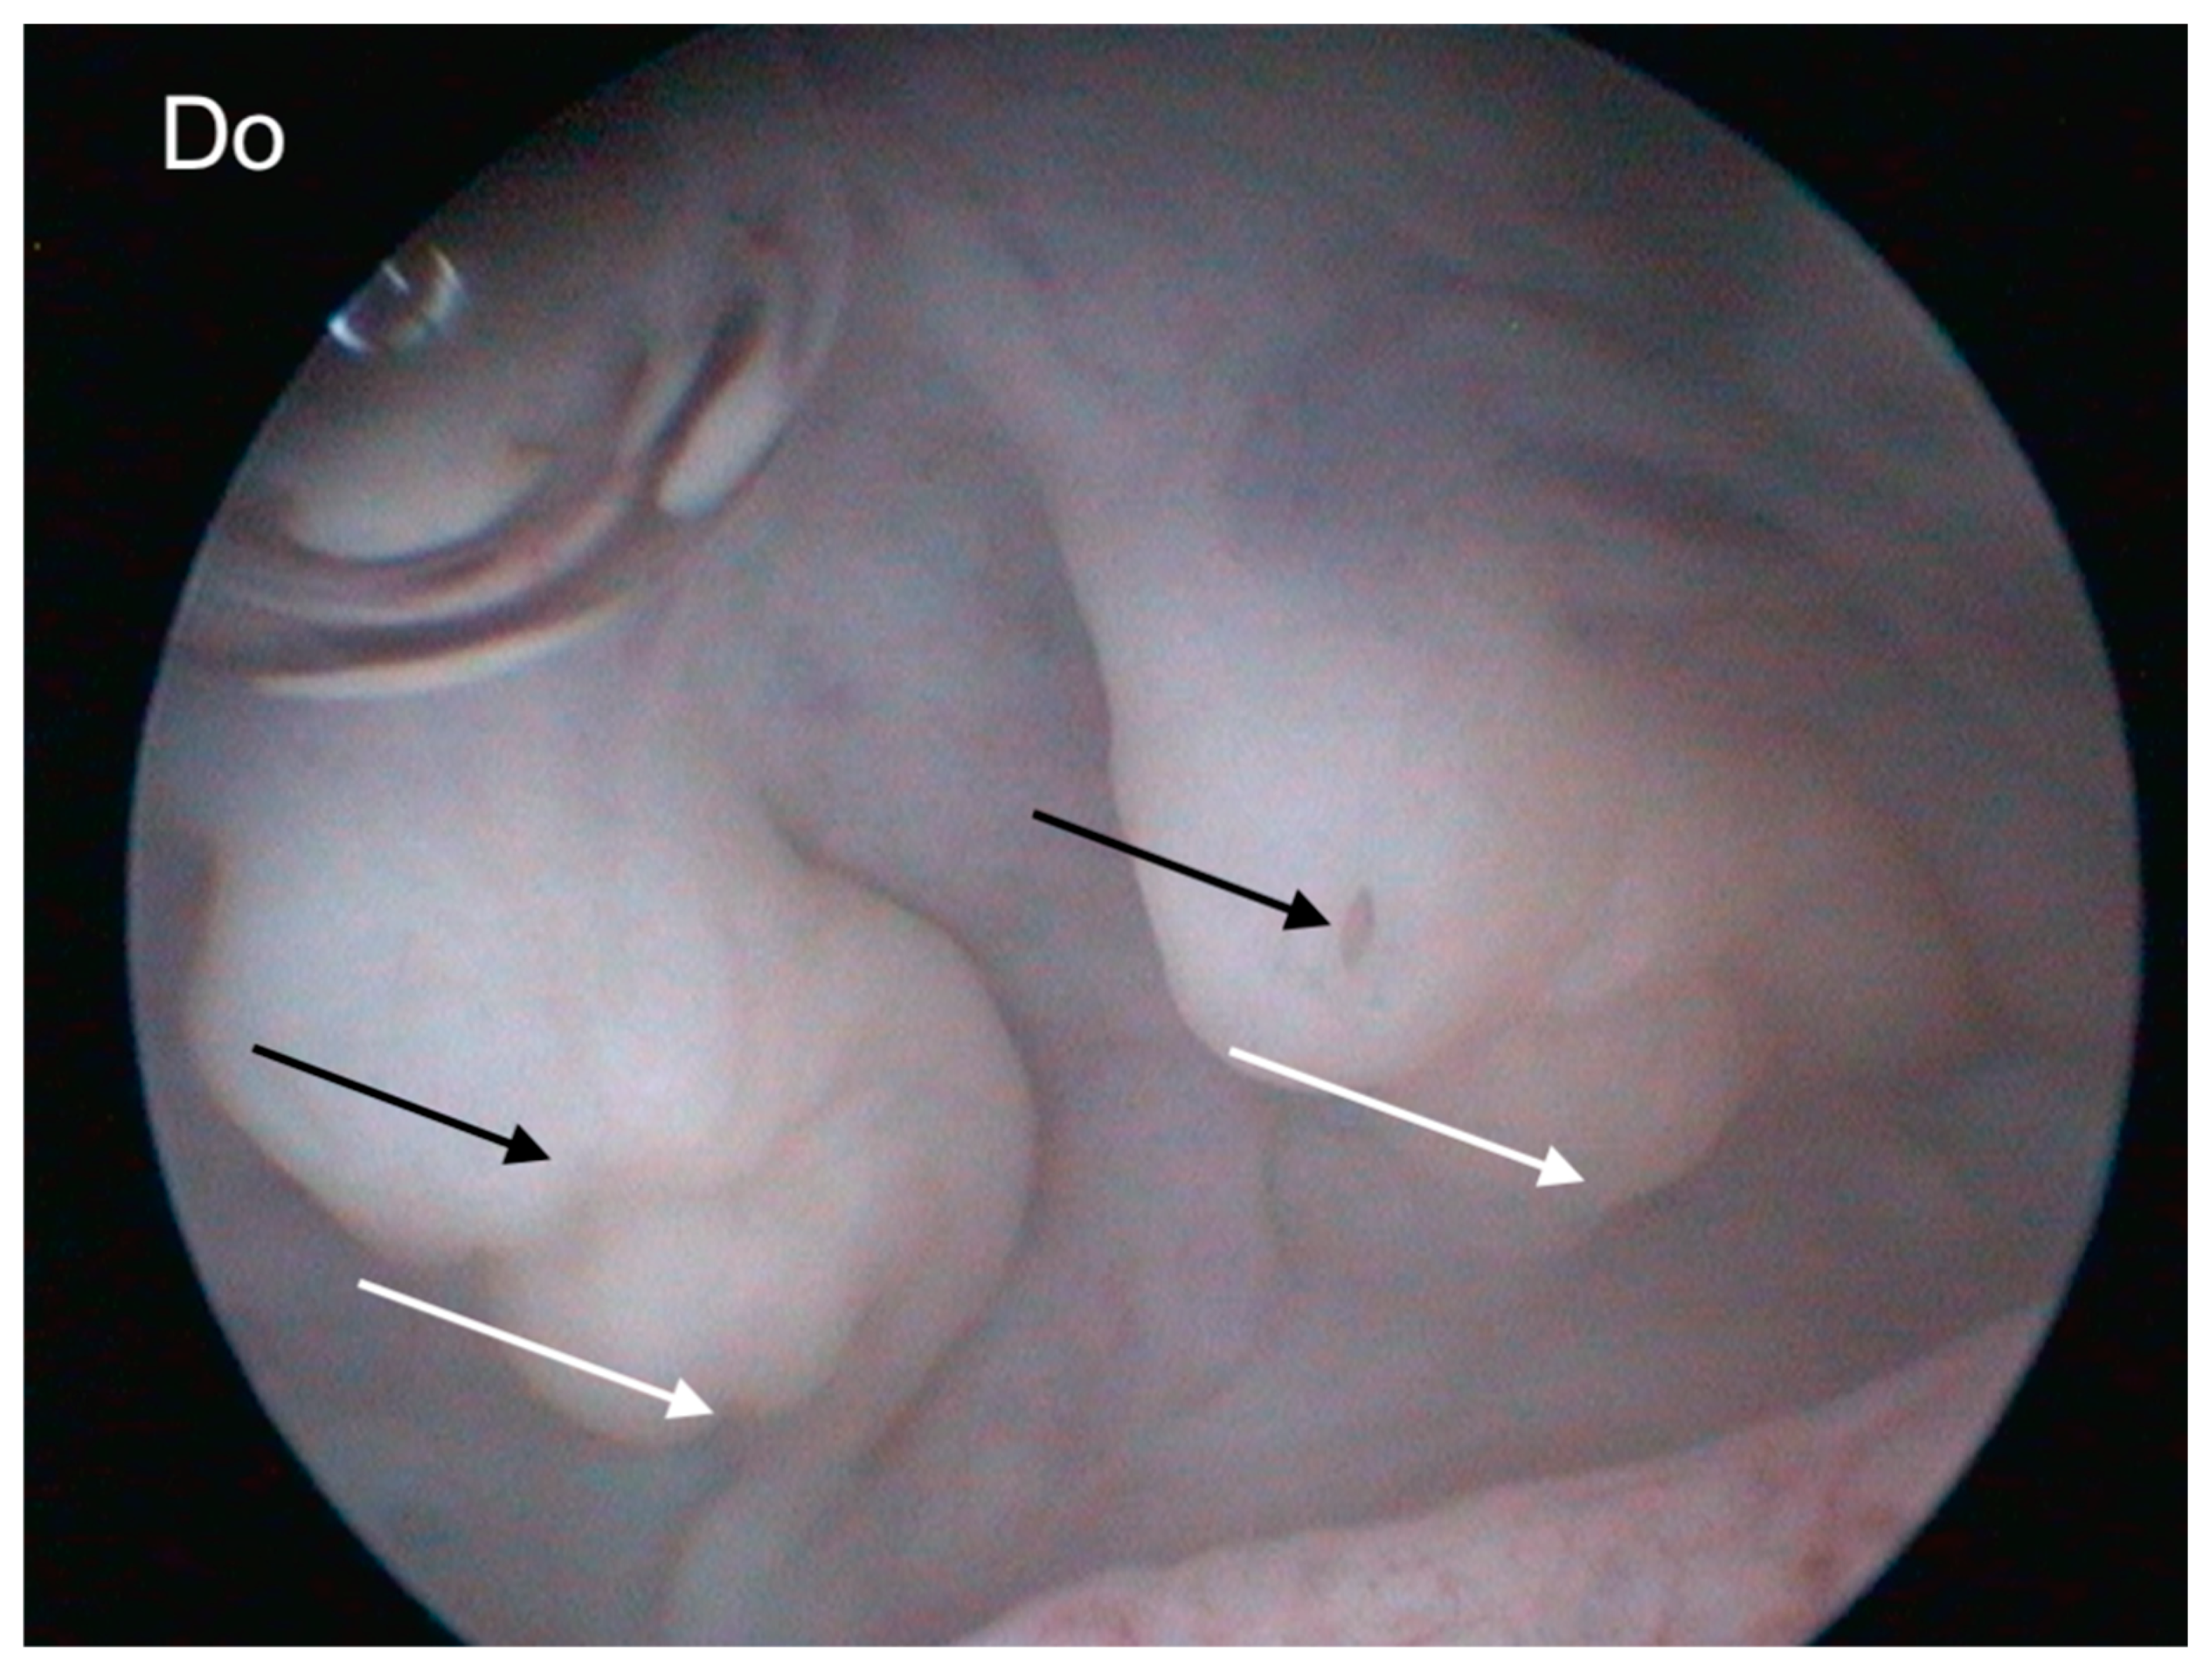

5.11. Cloacoscopy